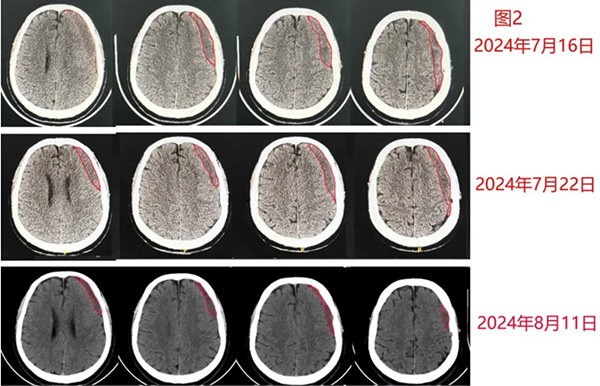

9月19日我在门诊遇到另一位让我印象深刻的患者。该患者从西北飞抵北京找我,看上去并不像得了颅内血肿的患者。他今年55岁,没有明确原因出现硬膜下血肿,8月16日左右在当地最大的医院做了钻孔引流手术,术后也确认血肿没有完全消失。当地医院的医生告知他,虽然血肿没有消失,但是血肿体积很小。建议他养一养,等血肿量大一点后再手术。但在我看来,这名患者的情况还是需要积极的去处理,因为此时颅内血肿估算至少超过20ml(图3)。

图3

患者当然也接受不了医生的这个“等待”疗法,因此他千里迢迢赶到北京来找我治疗。他在年轻时因为病毒性脑炎接受大剂量激素冲击治疗,残余了2°股骨头坏死。因此他的治疗又不同于一般患者。我给了他一个药物治疗方案,希望他能够在我指导下治愈。